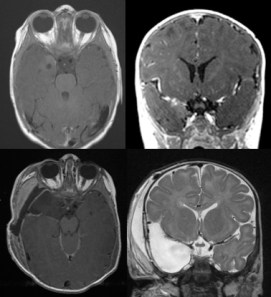

la clinique est souvent réduite à une augmentation rapide du périmètre crânien, parfois, une tuméfaction molle sous-cutanée lorsque la voûte est lysée ; au moment du diagnostic, il existe le plus souvent un tableau d’hypertension intra-crânienne souvent sévère.

dans les tumeurs gliales, une présentation épileptique est fréquente.